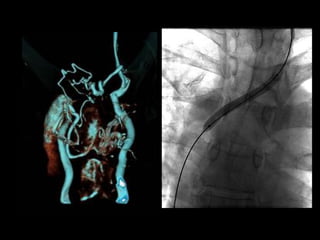

LUNG CA

with SVC syndrome